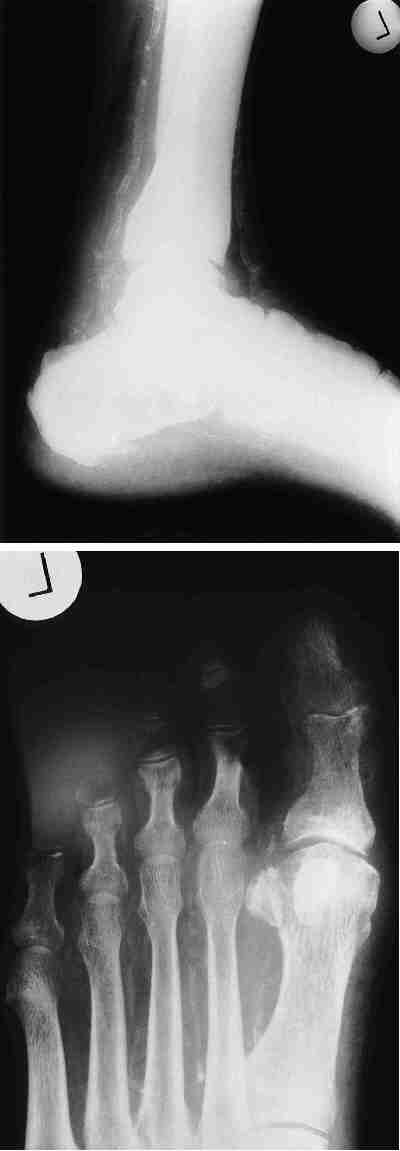

Diabetischer Fuß: Bildteil - Mediasklerose

Abb. 1: Ausgeprägte Mediasklerose (Mönckeberg-Sklerose) mit Nativ-Darstellung des Gefäßes im Röntgenbild bei langjährigem Diabetes mellitus ohne Nachweis einer arteriellen peripheren Durchblutungsstörung.